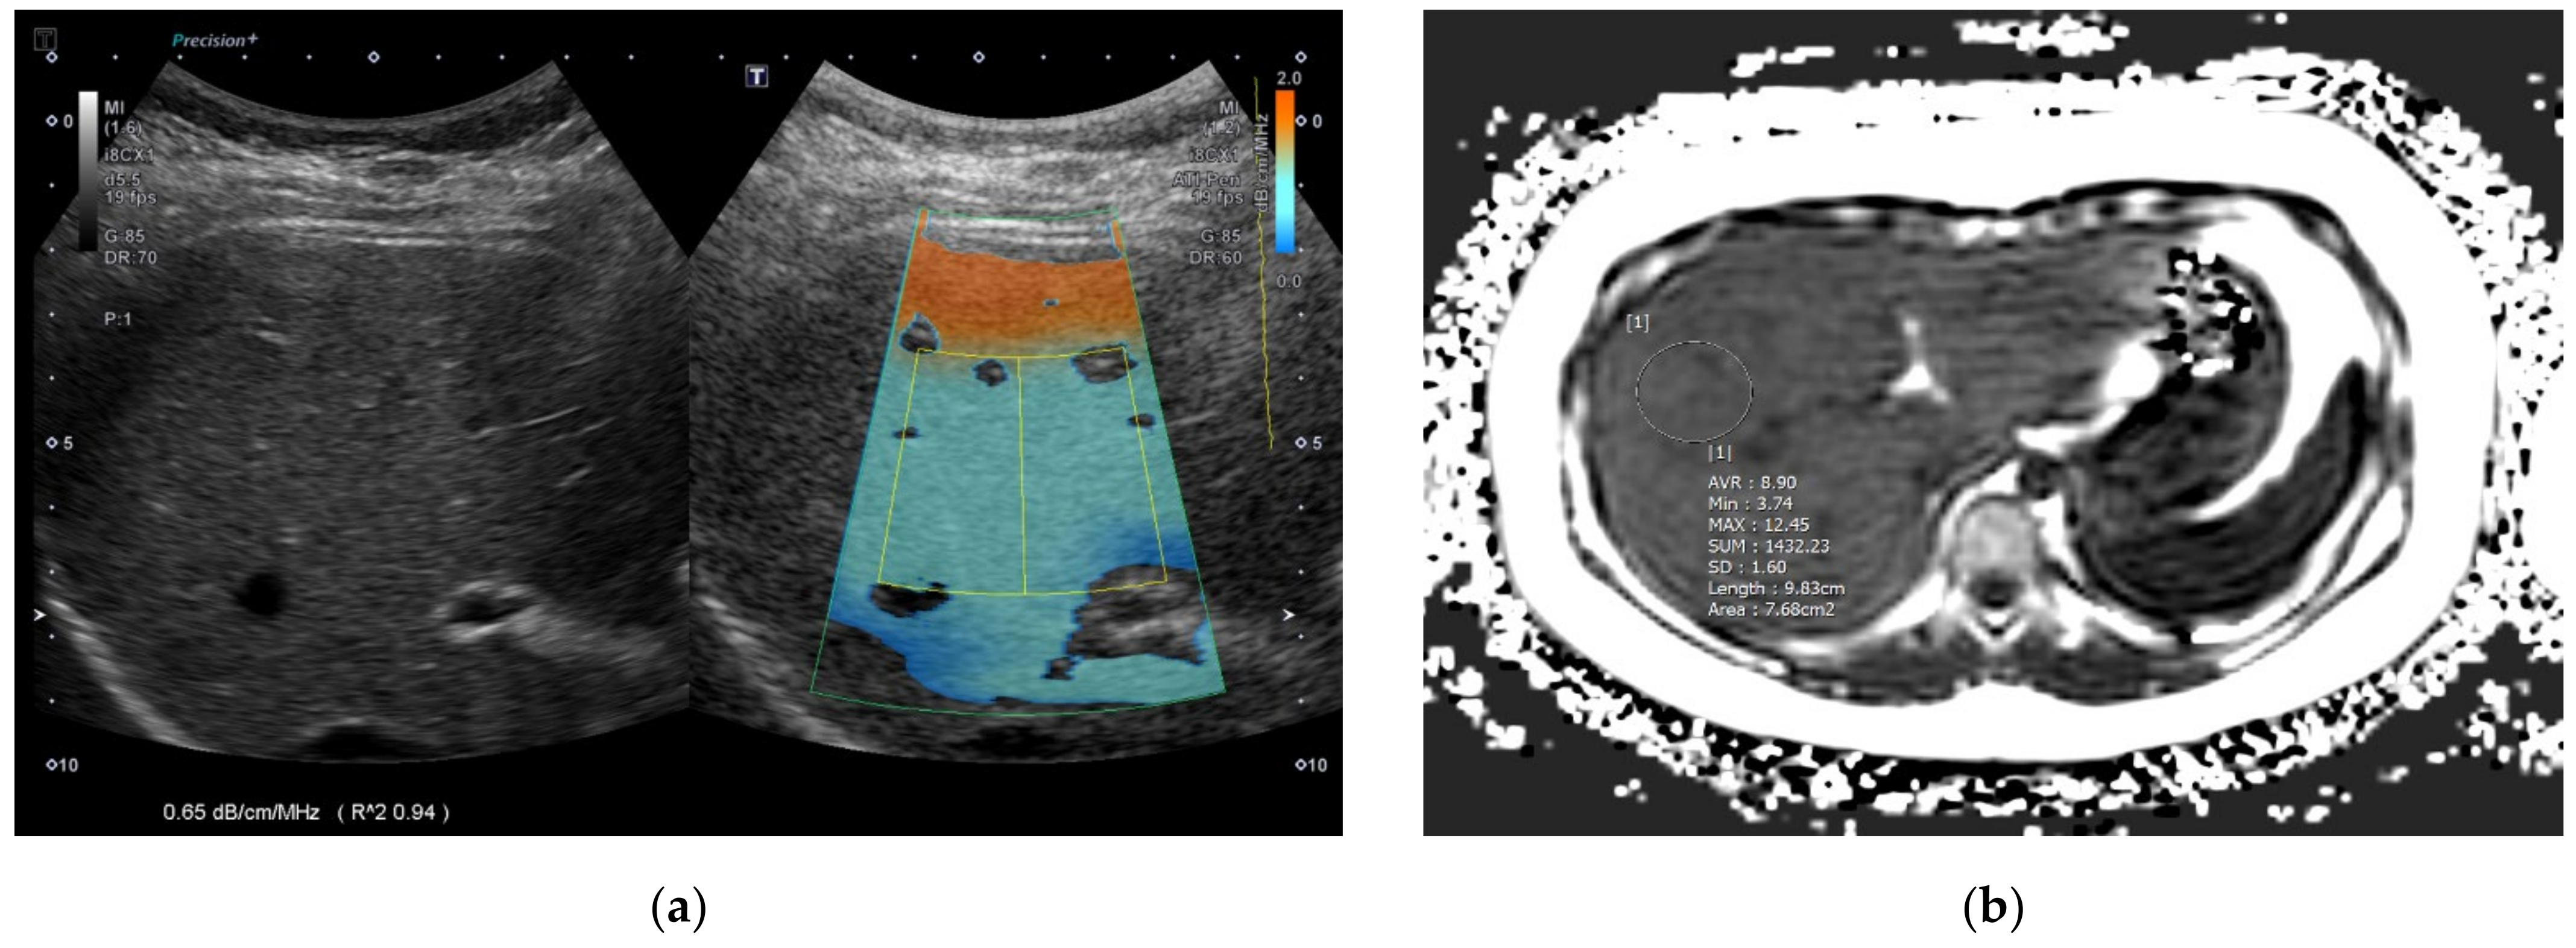

After the acquisition, the maximum longitudinal diameter of the right liver lobe (cm), PDFF (%), T2* (ms) value, and MRE (kPa) value of the liver were collected. To obtain PDFF, T2*, and MRE values, four ROIs were drawn in the liver avoiding hepatic vessels and artifacts using the axial slices of each sequence by an experienced pediatric radiologist and the mean value of the four measurements was used as a representative value (Figure 1 and Figure 2). Steatosis grades could be also categorized using cutoff values of PDFF identified in a previous study; S1 (mild) for PDFF > 6%~<17.5%, S2 (moderate) for PDFF ≥ 17.5%~<23.3%, and S3 (severe) for PDFF ≥ 23.3% [20].

2.3. ATI Acquisition

Figure 1. A 7-year-old girl in the mild fatty liver group according to grayscale US. (a) The ATI value was 0.65 dB/cm/MHz and (b) MRI-PDFF value was 8.9% (S1: PDFF > 6%). US: ultrasonography; ATI: attenuation imaging; MRI: magnetic resonance imaging; PDFF: proton density fat fraction.